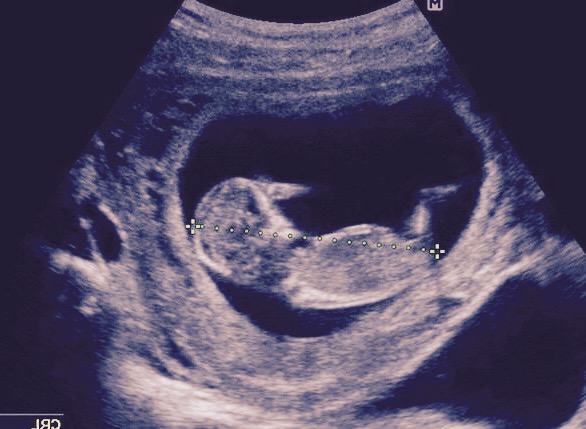

Taken at 12 weeks 5 days. Guesses PLEASE! I have gotten mixed reviews!

Attachment 31548

The first pic looks girly to me but then the second pic looks boyish. Sorry, I know that doesn't help!

Maybe boy based on second pic, but not the best pics, so could well be a girl too.